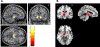

Results: The disease epicenter was identified in the left midbrain tegmental region. Compared with age-matched control subjects, patients with PSP-RS showed progressively widespread decreased SFC of the midbrain with striatal and cerebellar regions through direct connections and sensorimotor cortical regions through indirect connections. A correlation was found between average link-step distance from the left midbrain in healthy subjects and brain volumes in patients with PSP-RS (r = 0.38, P < 0.001).